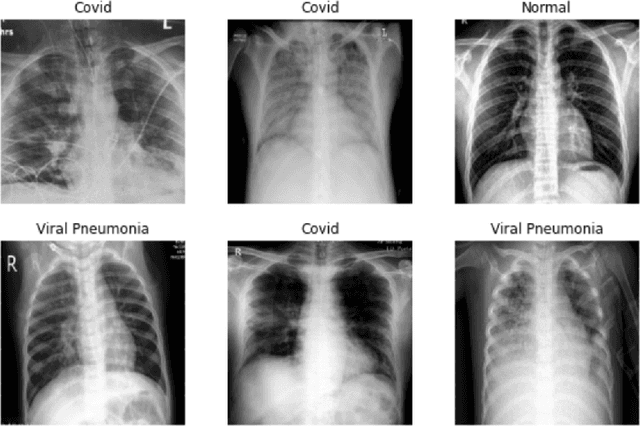

Abstract:In the current COVID-19 pandemic situation, there is an urgent need to screen infected patients quickly and accurately. Using deep learning models trained on chest X-ray images can become an efficient method for screening COVID-19 patients in these situations. Deep learning approaches are already widely used in the medical community. However, they require a large amount of data to be accurate. The open-source community collectively has made efforts to collect and annotate the data, but it is not enough to train an accurate deep learning model. Few-shot learning is a sub-field of machine learning that aims to learn the objective with less amount of data. In this work, we have experimented with well-known solutions for data scarcity in deep learning to detect COVID-19. These include data augmentation, transfer learning, and few-shot learning, and unsupervised learning. We have also proposed a custom few-shot learning approach to detect COVID-19 using siamese networks. Our experimental results showcased that we can implement an efficient and accurate deep learning model for COVID-19 detection by adopting the few-shot learning approaches even with less amount of data. Using our proposed approach we were able to achieve 96.4% accuracy an improvement from 83% using baseline models.